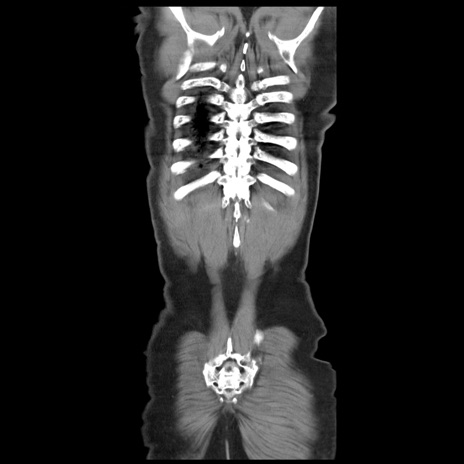

症例20(冠状断像)

【症例】 60歳代男性

【主訴】 腹部膨満、嘔吐

【現病歴】5日前頃より倦怠感を認め食事量減少し4日前の朝嘔吐、食事摂取困難となった。 3日前近医受診し点滴施行され整腸剤などを処方された。 当日他院を受診し、腹部膨満著明、炎症反応の上昇(CRP10.8、WBC11200)あり、紹介受診となる。

【身体所見】 意識JCS1 受け答えがはっきりしないBP 111/57mHg、 P 67bpm、、BT35.2°C、SpO2 97%(RA)、 腹部:膨隆、打診で鼓音あり、全体的に圧痛有り、腸蠕動音(-)、反跳痛ははっきりせず。

【データ】WBC 11400、CRP 14.20